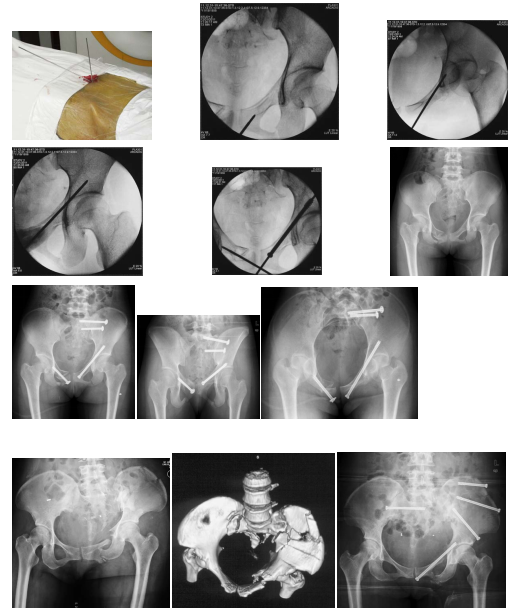

骨盆骨折的闭合复位经皮通道螺钉微创治疗技术

以下图片是我科骨盆骨折的闭合复位经皮通道螺钉微创治疗技术的一例患者资料

图:A、B、C、D术前X光片

图:E、F、G术前CT

图:T术后X光片

图:U、V、W、X、Y、Z术后CT